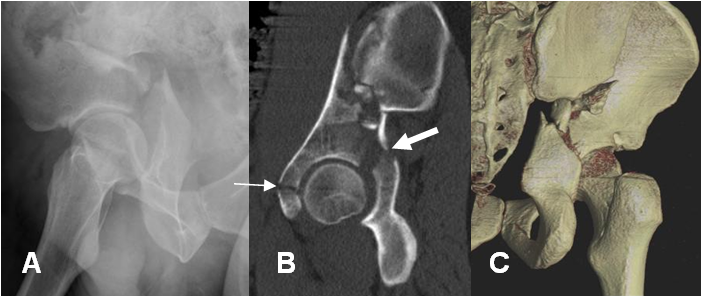

Fig 59. Fragmentos libres.

A y B: TAC axial. Fracturas del acetábulo no mostradas, con fragmentos libre intra-articulares.

A: RC axial de cadera. Fractura conminuta e impactada, del techo acetabular y el iliaco.

B: TAC reconstrucción sagital. Fractura conminuta, con compromiso anterior (Flecha delgada) y posterior (Flecha gruesa) del acetábulo.

C: TAC reconstrucción 3D, donde se confirman los hallazgos.